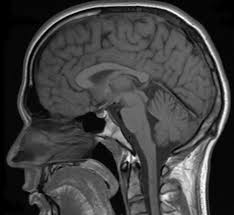

While the body of an Alzheimer’s patient deteriorates, the brain plays host to an orgy of activity. A healthy, adult brain weighs about three pounds, yet it consists of roughly a hundred billion cells, or neurons, which are linked to one another by pathways. The brain serves as the center for all major bodily functions, as well as systems related to emotion, perception, thought, and memory. Everything works together in a harmonized symphony, and yet the brain allows one to act on impulse, extemporaneously, at a moment’s notice. Most of the time, we take for granted how well the brain works. Only when it breaks down do we realize how good we had it in the first place.

I imagine that this is a malady that plots in the middle of the night, enacting its grand design so silently that an official diagnosis requires evidence of both plaques and tangles (types of protein), which can only be obtained through physical examination of the brain. In this case, death comes before diagnosis. Rather than living up to its symbol of life, the brain is now a harbinger of death, its two halves folding together to form a coffin. I often wonder how it came to pass that both my grandparents suffered from memory loss. Was there a perfidious strand of the disease in the gene pool that continues to writhe in my own genetic makeup? Is it inevitable that it will be my turn someday? There must be a reason why their brains were so hospitable to conquest. Come to think of it, they always did teach me that guests of the house should be revered like gods.